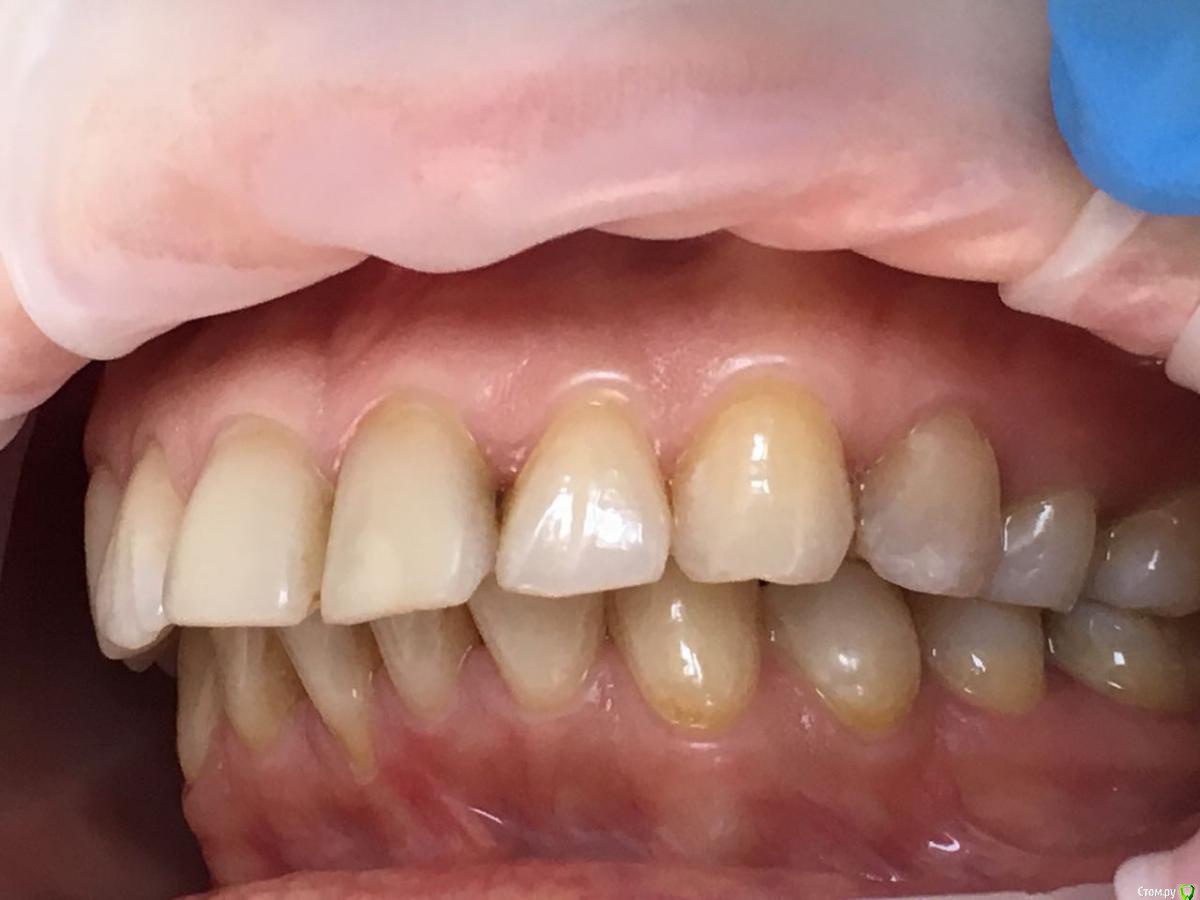

Kema Опубликовано 25 сентября, 2018 Автор Поделиться Опубликовано 25 сентября, 2018 Хочу улучшить эстетический вид.Лет 15 назад носила брекеты только на нижней челюсти. Через 1.5 года сняла так как не было результата. На верхнюю челюсть ортодонт ставить не спешил, говорил внизу надо расправить скученность. Ещё говорил, что у меня нижняя челюсть недоразвита. Ссылка на комментарий

Kema Опубликовано 25 сентября, 2018 Автор Поделиться Опубликовано 25 сентября, 2018 У меня нет нижней правой шестёрки. Правая восьмёрка подвинула семёрку, семёрка наклонилась. Левая ретинированная восьмёрка удалена. На правой стороне жевать неудобно. Ещё верхние зубы наклонились вперёд. Начитавшись про ортогнатические операции хотела узнать показана ли мне она. Ссылка на комментарий